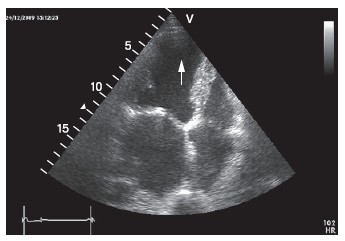

Длительно существующие пристеночные тромбы имеют четкие ровные контуры, широко предлежат к стенке желудочка, характеризуются достаточно высокой акустической плотностью, сопоставимой с плотностью нормально сокращающегося миокарда [20]. Такие тромбы играют формообразующую роль и укрепляют стенку аневризмы [21]. Трабекуляция и дополнительные хорды в области верхушки ЛЖ могут приводить к ложной диагностике тромбов. Внутрисердечные тромбы следует отличать от реверберации, которая имеет вид выпуклого в полость желудочка образования с радиальной исчерченностью (рис. 10). Краевая поверхность тромба чаще более контрастна и представляет собой выпуклые и вогнутые участки, тогда как при реверберации ее свободный край всегда выпуклый и в отличие от тромба не имеет тесной связи со стенкой сердца [22]. При обнаружении подозрительных на тромбы структур необходимо получить их изображение из различных сечений. Проведение исследования оправдано не только в традиционной серой шкале, но и с использованием режимов расцвечивания («колоризации») изображения, которые позволяют глазу исследователя воспринимать большее количество оттенков, чем при серошкальном изображении (см. рис. 9, г).

Рисунок 10. Эффект реверберации в области верхушки левого желудочка создает ложное впечатление о наличии тромба (стрелка) у больного острым инфарктом миокарда.